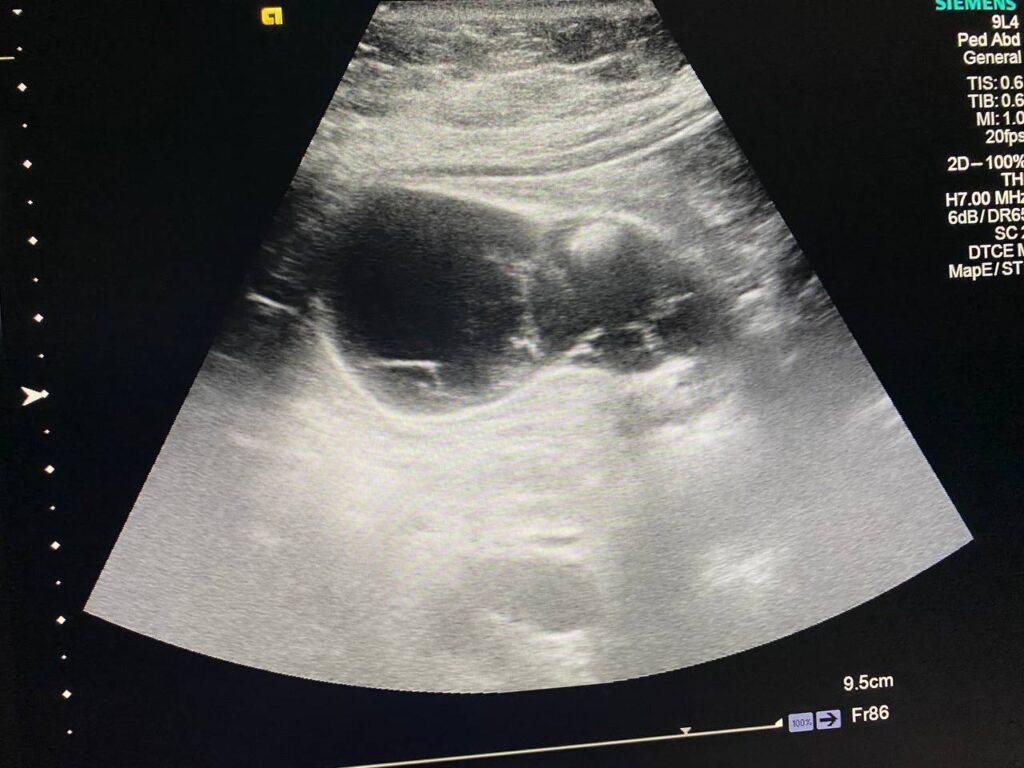

U/S : Gall bladder : distended , contain stone 9mm , full with heterogenous fluid , contain multiple honeycomb septations , also associated with pericholecystic edema 3.5mm , picture mostly of acute on chronic cholecystitis , please for further study normal common bile duct